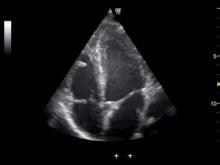

Cardiology (heart)

Echocardiography is an essential tool in cardiology, assisting in evaluation of heart valve function, such as stenosis or insufficiency, strength of cardiac muscle contraction, and hypertrophy or dilatation of the main chambers. (ventricle and atrium)